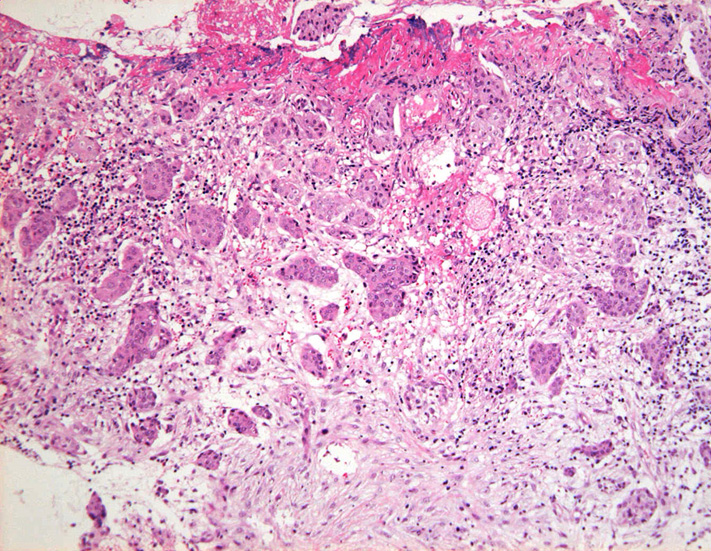

S状結腸粘膜生検組織所見:

粘膜筋板直下に小型胞巣を作って浸潤し炎症性の間質をともなう。 浸潤性増殖のわりに細胞は均一, そんなに異型性も強くない。apoptosisに陥った細胞が散在する。部位によっては胞巣状増殖細胞は細胞間橋がありそうな扁平上皮様に見える。深いところは線維性間質が増えてきて細胞は索状となりcarcinoidなども鑑別候補となるかもしれない。明らかな腺管形成, 粘液産生はみられない。35歳男性, わりとおとなしい扁平上皮癌様の組織か?と生検初見時に考えられた。desmoplasticな間質にもよく観察するとバラけた細胞異型が認められる。 (腫瘍胞巣①, ③)